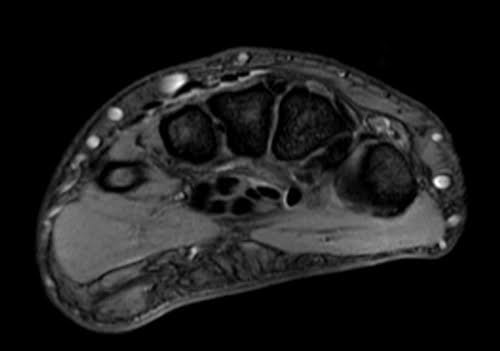

MRI wrist axial medic image 3 - MRI